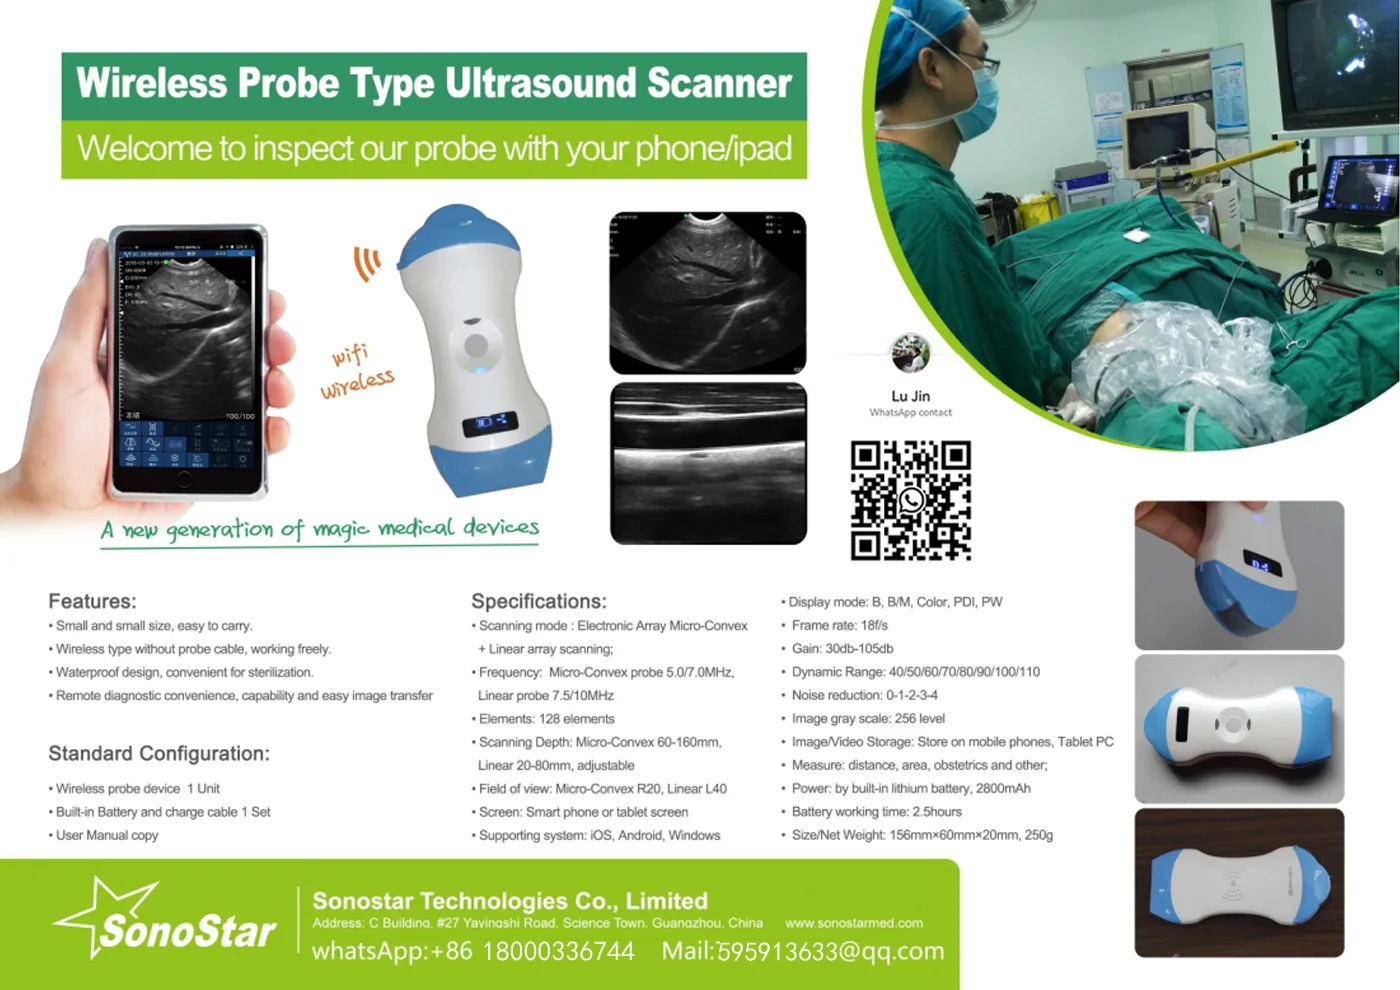

Linear Probe Parameters

-Scanning mode: Electronic array

-Display mode: B, B/M

-Probe element: 80

-Channel of RF circuit board: 16

-Frequency: 7.5MHz/10MH

-Scan depth: 20/40/60/100mm

-Head width: 40mm

-Image Adjust: BGain, TGC, DYN, Focus, Depth, Harmonic, Denoise, Color Gain, Steer, PRF

-Cineplay: auto and manual, frames can set as 100/200/500/1000

-Puncture assist function: the function of in-plane puncture guide line, out-of-plane puncture guide line, automatic blood vessel measurement.

-Measure: Length, Area, Angle, heart rate, Obstetrics

-Image save: jpg, avi and DICOM format

-Image frame rate: 18 frames / second

-Battery working time: 3~5 hours(according to different probe and whether keep scan)

-Battery charge: by USB charge or wireless charge, take 2 hours

-Dimension: 156×60×20mm

-Weight: 220g~250g

-Wifi type: 802.11g/20MHz/5G/450Mbps

-Working system: Apple iOS and Android, Windows 10 system

Linear Probe Pictures:

This machine can be used for both humans and animals: